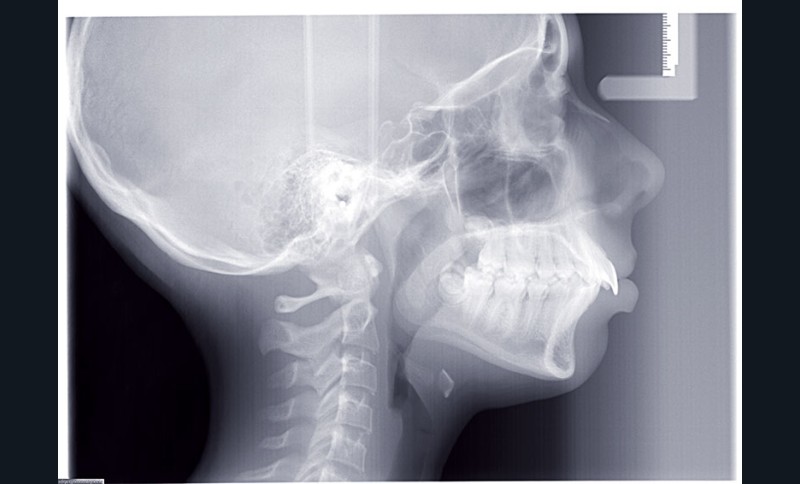

Elle présente une classe II squelettique par rétrognathie mandibulaire et une classe II dentaire molaire et canine droite et gauche associée à une biproalvéolie incisive maxillaire et mandibulaire.

L’environnement vertical est normodivergent.

Le contexte facial est délicat avec un profil cis-frontal, un angle naso-labial très ouvert et un sillon labio mentonnier marqué avec retour de la lèvre inférieure en arrière des incisives maxillaires.

Le pronostic de correction de la classe II est favorable mais il est très important de souligner la vestibuloversion incisive mandibulaire et le risque parodontal associé (fig. 1 à 3).